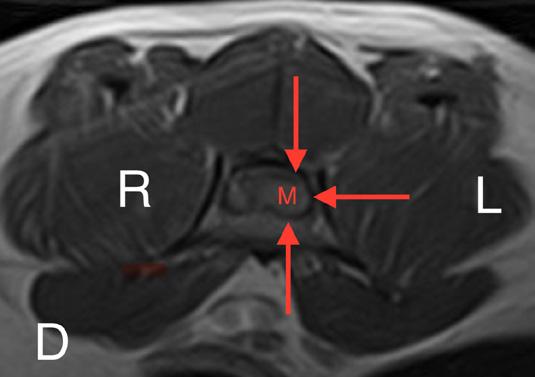

Las pruebas diagnósticas realizadas incluyeron análisis de sangre, radiografía laterolateral de tórax y ecografía abdominal, sin resultar en alteraciones significativas. La serología frente al virus de la leucemia e inmunodeficiencia felina resultó positiva para esta última. En el estudio de resonancia magnética (RM; Fig. 2) de la región toracolumbosacra (Toshiba Vantage Elan 1.5 T: Adquisición de planos transversal, sagital y coronal ponderados en T1 pre y post-contraste intravenoso con gadolinio, así como planos ponderados en T2 y STIR) se cuentan 6 vértebras lumbares, lo cual es compatible con anatomía de transición en la región lumbar, como hallazgo incidental. En el lado izquierdo del canal vertebral, desde el tercio craneal de la vértebra L5 hasta el tercio caudal de la vértebra L6 se encuentra una lesión con aspecto alargado y de base ancha, con márgenes mal definidos e irregulares, distribución posiblemente extradural y/o intradural/extramedular, causando compresión severa de la médula espinal, que aparece desplazada hacia el lado derecho. En cuanto al patrón de intensidad de la señal, este fue hiperintenso de forma homogénea en las secuencias ponderadas en T2 e isointenso en las secuencias ponderadas en T1, con un realce homogéneo y focal en la región media de la vértebra L6. La lesión se extiende parcialmente en el foramen intervertebral izquierdo entre las vértebras L5 y L6 y se aprecia siringomielia leve, que puede ser un proceso secundario a la compresión de la médula espinal por parte de la lesión, más caudalmente a nivel lumbar.

Figura 2. Imágenes de RM postcontraste en las que se identifica una lesión de forma alargada y ancha en su base, con distribución posiblemente extradural y/o intradural/extramedular a nivel de la vértebra L6 (flechas rojas). (A) Secuencia dorsal en STIR. (B) Secuencia transversal en T2. Nótese la compresión severa a la que es sometida la médula espinal (flecha verde). (C) Secuencia transversal en T1 precontraste. (D) Secuencia transversal en T1 postcontraste. M: masa; SC: médula espinal; R: derecha; L: izquierda.